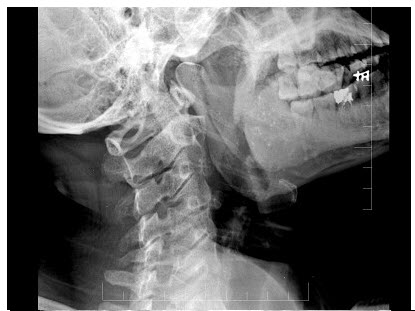

C.门静脉栓塞